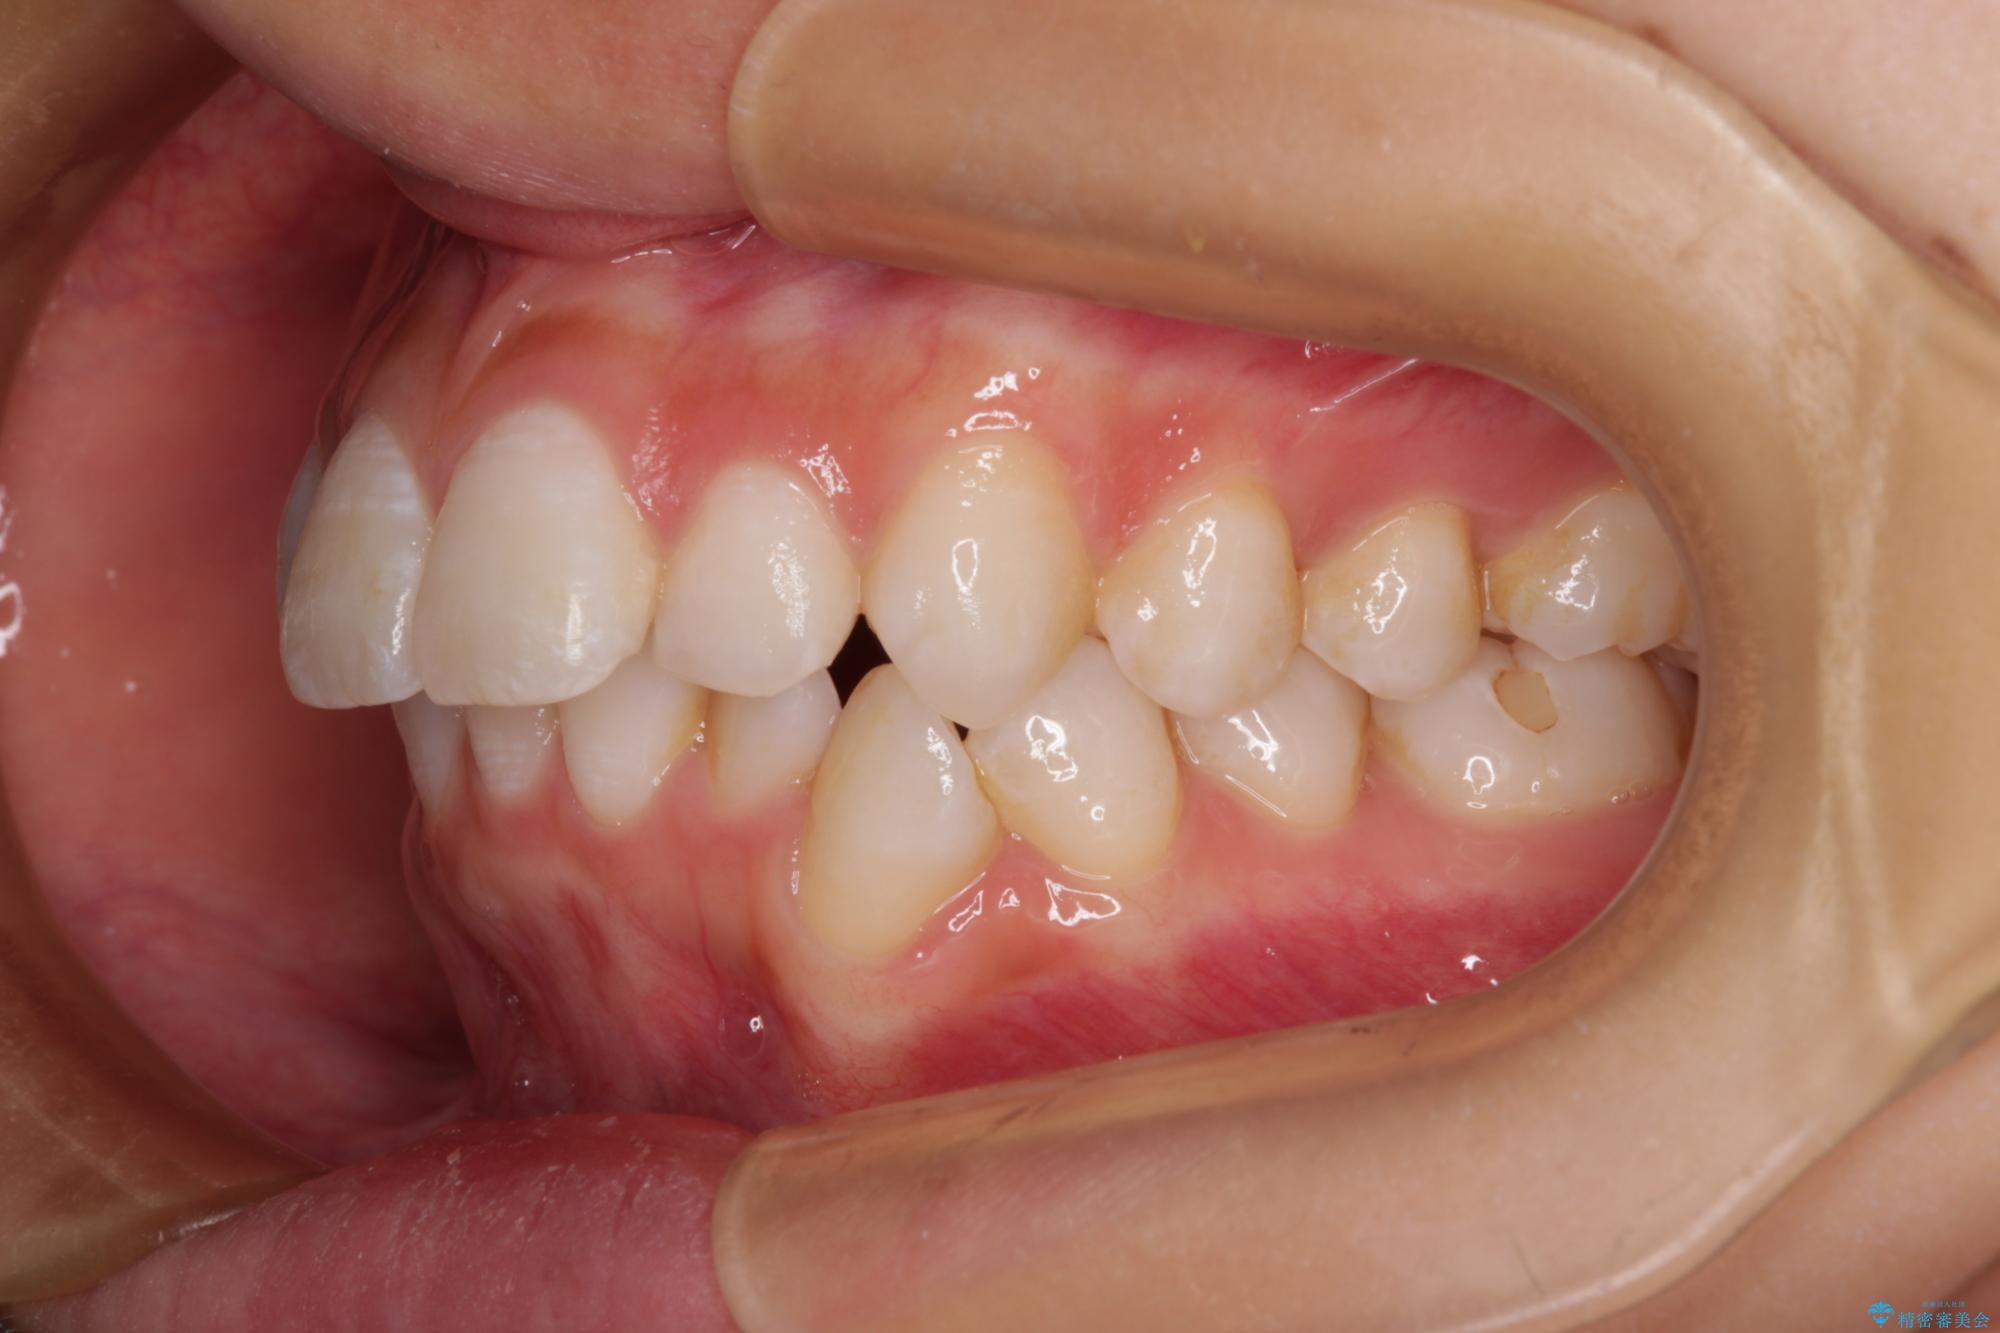

- 口を閉じたときに飛び出してしまう上顎前歯を気にして来院された患者様です。

下顎はデコボコが気になっていたため、上下左右第一小臼歯4本を抜去して、ワイヤー装置にて口元の突出感を改善するよう矯正治療を行うこととしました。